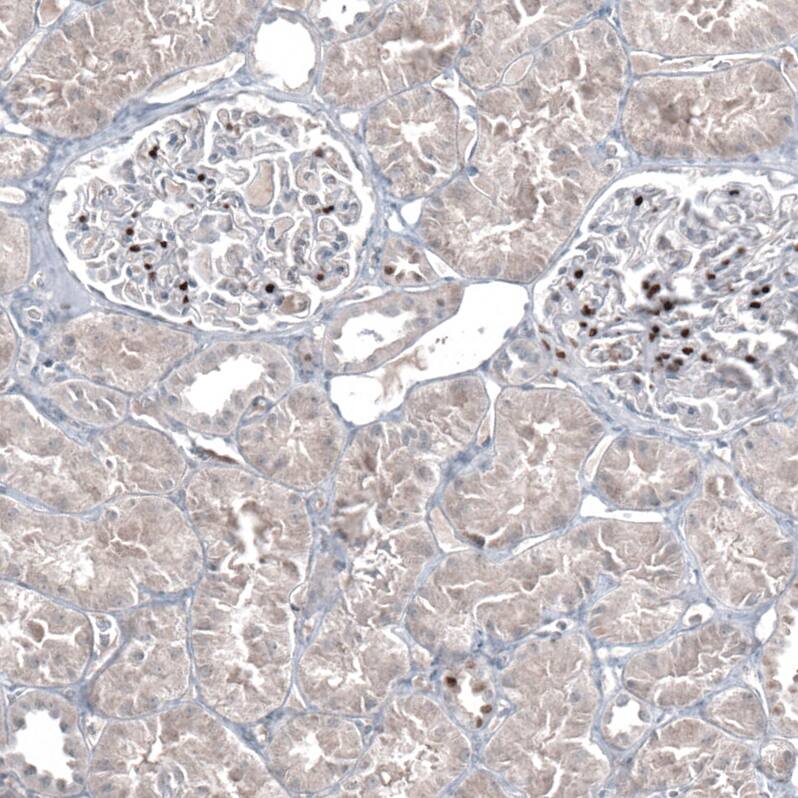

Immunohistochemistry-Paraffin: GATA-3 Antibody [NBP3-44195]

Staining of human kidney shows strong nuclear positivity in a small subset of cells in glomeruli.Applications for GATA-3 Antibody (CL8660) - Azide and BSA Free